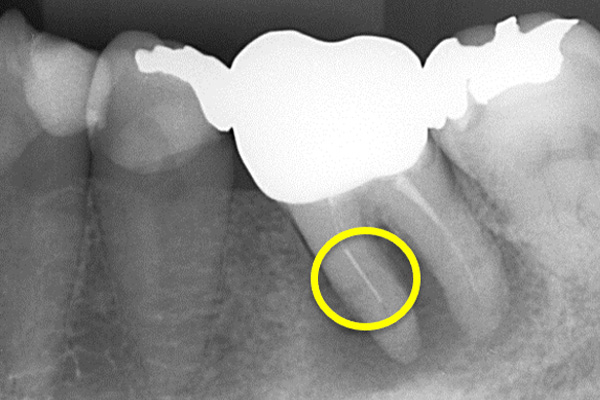

根の横に誤った穴をあけてしまい、気づかずに薬を入れてしまっている。また、器具が破折し、根の先に飛び出ている。

精密根管治療治療終了時歯の側面の穴と根尖はMTAにより緊密に封鎖した。

※本来の根管に薬が入ってることがわかります。